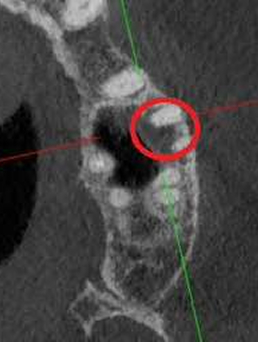

Проблема: У пациента отек щеки, боли самопроизвольные, усиливающиеся при приеме пищи, неудачное первичное лечение зуба (старыми методами).

Лечение: Проведено эндодонтическое перелечивание зуба под дентальным микроскопом, что позволило точно выявить анатомические особенности корневых каналов и устранить последствия ранее некачественного лечения. После купирования воспалительного процесса (киста) каналы герметично запломбированы. Коронковая часть зуба восстановлена для сохранения функции и герметичности до этапа постоянного протезирования.